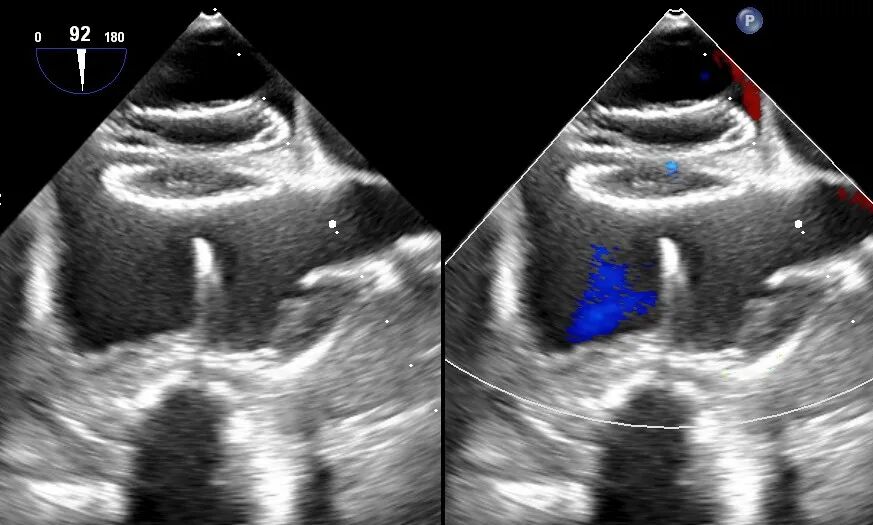

??术中经食道心脏彩超提示封堵器形态良好,无明显反流

??术中采用经胸骨旁3cm的手术切口暴露右心房,在精确食道超声引导下,带有封堵器的输送鞘直接经右心房送入房间隔缺损部位,封堵器的两片“小伞”将像三明治一样将缺损完全封闭。食道超声反复确定封堵器稳固后撤出“封堵器保险绳”,手术顺利完成。术中心脏操作过程仅用10分钟左右,术后患者于手术室即刻拔除气管插管,安返病房。术后吴大妈恢复迅速,第2天就能下床活动,目前已经顺利出院。